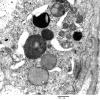

PERIPHERAL NEUROPATHY

17 TOXIC NEUROPATHIES

Amiodarone (2)